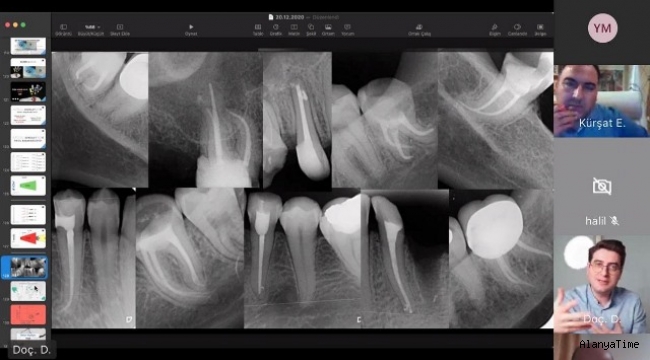

Bu süreçte çalışmalarına ve bilimsel toplantılarına internet üzerinden hız kesmeden devam eden ALKÜ, bünyesinde bulunan Diş Hekimliği Fakültesi yürütücülüğünde düzenlenen “Büyütme ve Aydınlatma Altında Kök Kanal Şekillendirmesi” başlıklı bilimsel webinara ile bir yenisini daha ekledi. ALKÜ’nün yanı sıra Akdeniz Üniversitesi, İstanbul Medipol Üniversitesi, Karadeniz Teknik Üniversitesi ve İstanbul Medeniyet Üniversitesi tarafından ortaklaşa düzenlenen panele İstanbul Medipol Üniversitesi’nden Doç. Dr. Mustafa Gündoğar ile İstanbul Medeniyet Üniversitesi’nden Doç. Dr. Taha Özyürek konuşmacı olarak katılırken, ALKÜ Diş Hekimliği Fakültesi Dekanı Prof. Dr. Kürşat Er de panelin yürütücülüğünü üstlendi.